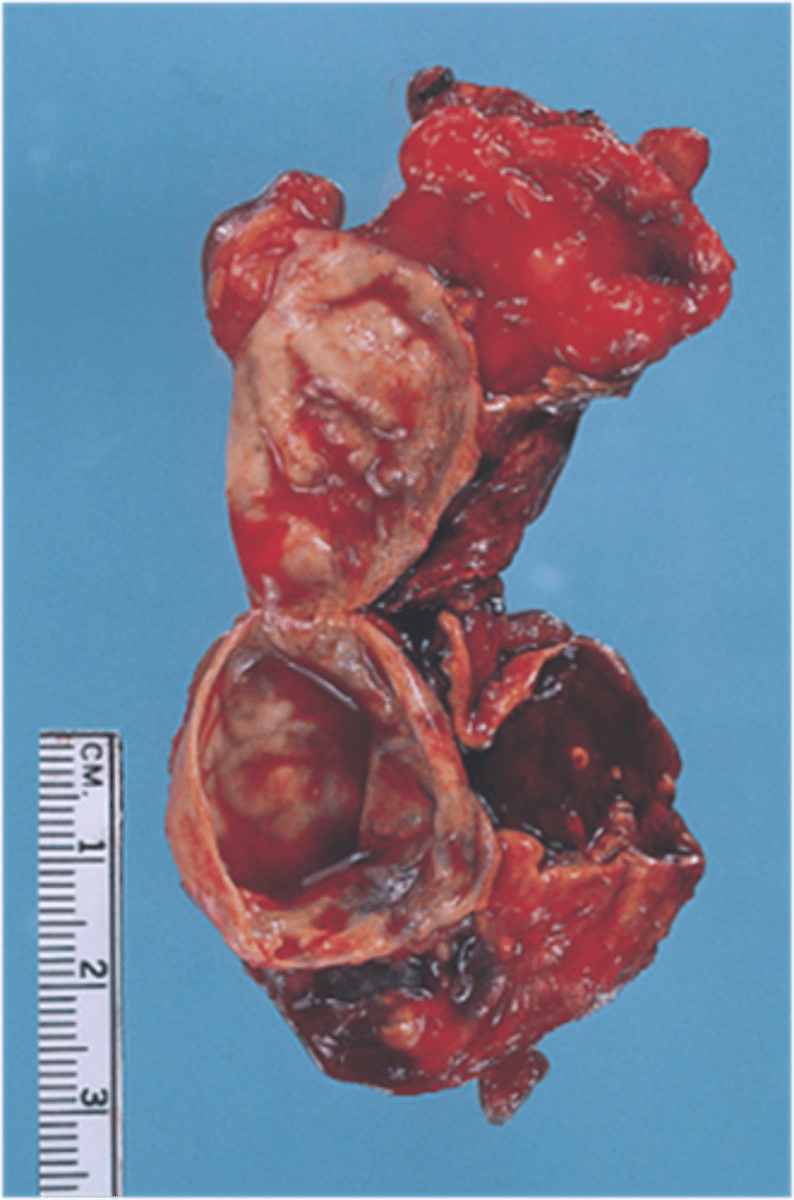

Benign adrenal cyst

Identify the pathology